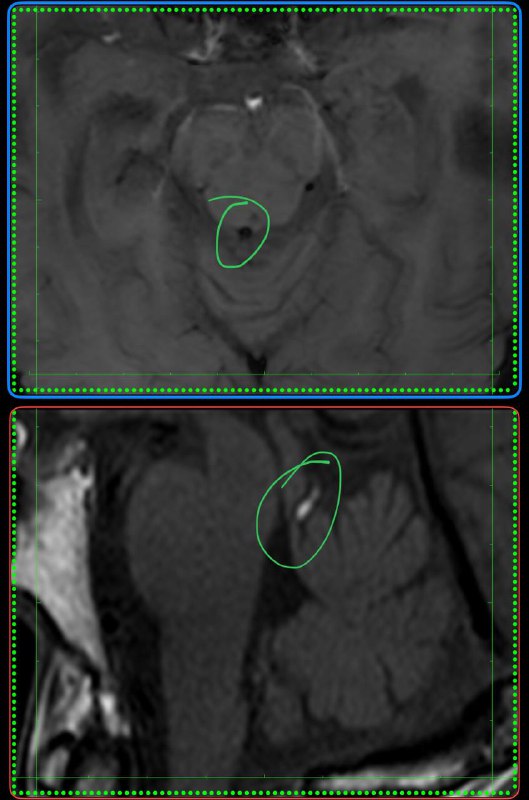

Подборка с рутины. Что видел за последние несколько дней.

Мелкий фокус аденомиоза.

Субэпендимальные узелки при туберозном склерозе у плода.